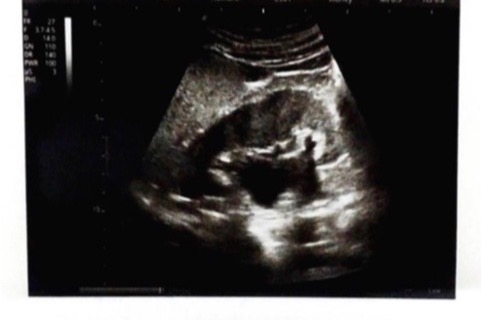

Uncle Tony lives in a Nicaragua that lacks modern medical care and his Diabetes was not properly managed. Sadly, his diabetes progressed to the point where his kidneys are severely compromised.

His doctor say that his kidneys are obstructed and the ONLY option is surgery. Otherwise, it's only a matter of time before his kidneys fail.